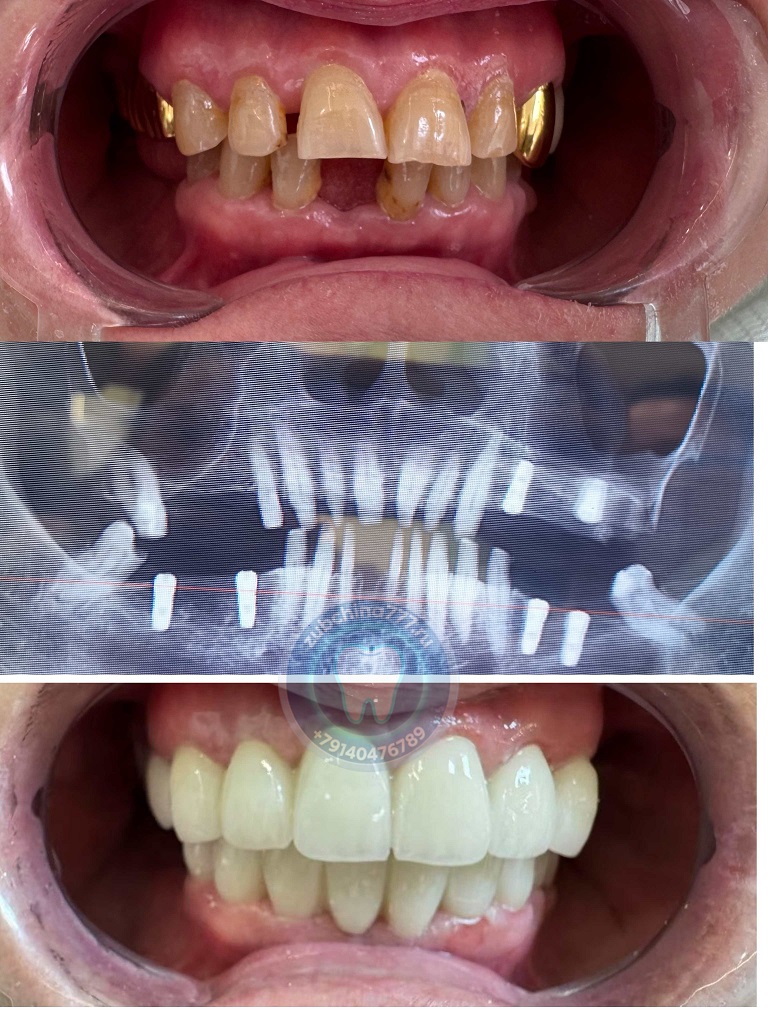

Фотографии пациентов ДО и ПОСЛЕ лечения и протезирования зубов в Хэйхэ